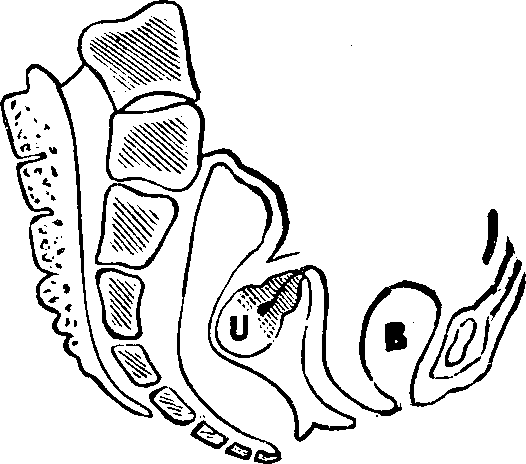

Fig. 10. Flexion, u, Uterus, B, Bladder.

Fig. 11. Version, u, Uterus, B, Bladder.

Flexions and Versions of the Womb. Flexion of the uterus, in which it is bent upon itself, as illustrated in Fig. 10, produces a bending of the cervical canal, constricting or obliterating it, and thus preventing the passage of spermatozoa through it. Version of the uterus [pg 710]in which its top, or fundus, falls either forward against the bladder (anteversion), as illustrated in Fig. 11, or backward against the rectum (retroversion), may close the mouth of the uterus by firmly pressing it against the wall of the vaginal canal, and thus prevent the passage of spermatozoa into the womb. 'The treatment of these several displacements will be considered hereafter. We may here remark, however, that they can be remedied by proper treatment. Our mechanical movements, manipulations, and kneadings are invaluable aids in correcting these displacements.